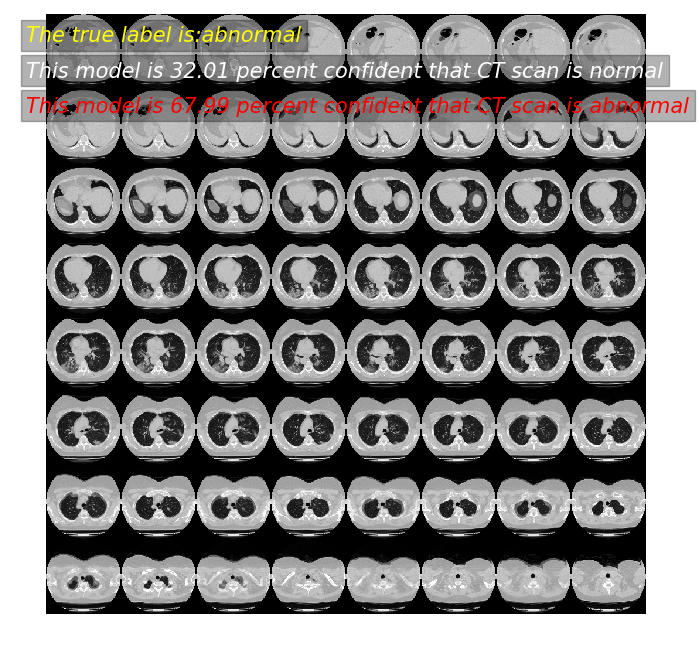

predictor(11)

模型预测: 32.01 概率,这张CT normal

模型预测: 67.99 概率,这张CT abnormal

真实标签为: abnormal